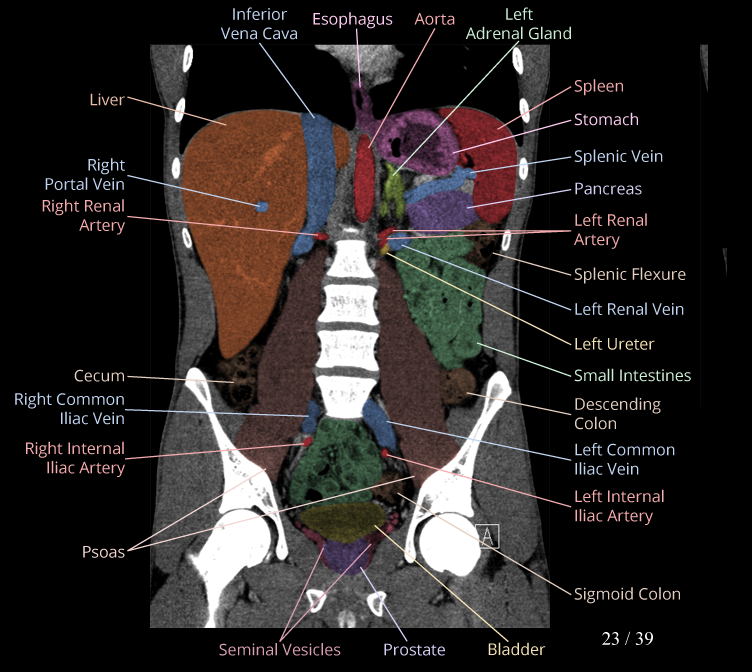

Body

Covers abdominal CT anatomy.